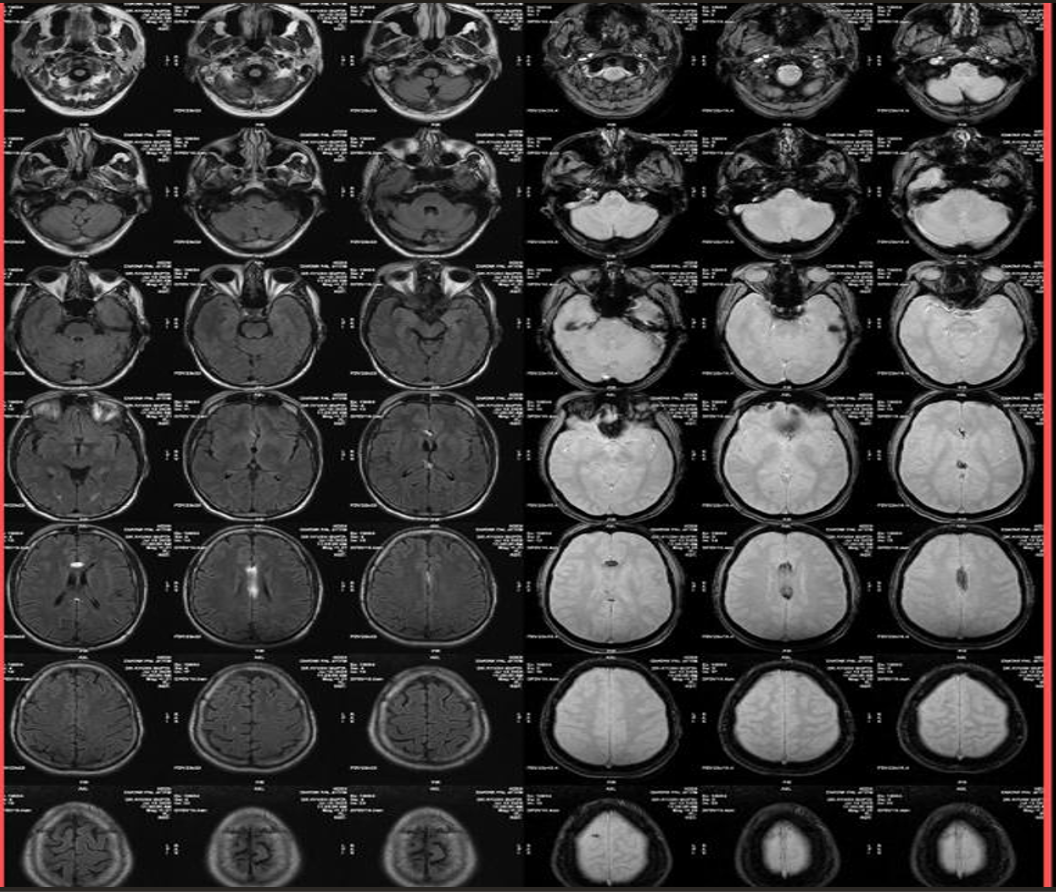

Imaging Findings-

- CT

- Well-defined, homogeneous, hypodense lesion (-50 to -100 HU, consistent with fat).

- May show peripheral or central calcifications (~50% cases).

- No enhancement with contrast.

- MRI

- T1-weighted: Hyperintense (fat signal).

- T2-weighted: Variable, usually hyperintense; may show chemical shift artifacts.

- Fat-suppressed sequences: Complete signal suppression confirms fat composition.

- Post-contrast: No enhancement.

- Often associated with:

- Corpus callosum agenesis/dysgenesis

- Interhemispheric cysts

- Calcifications (better on CT)